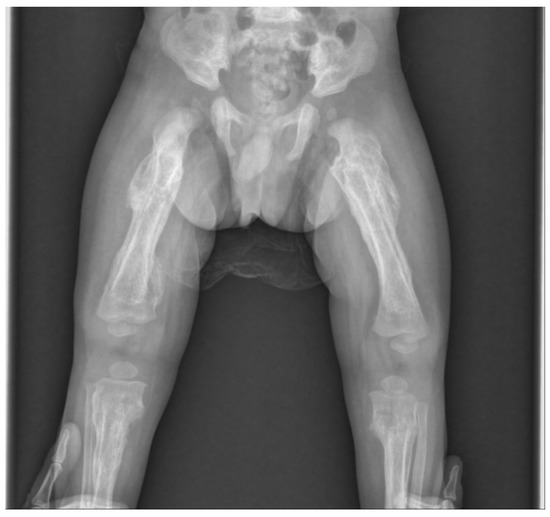

Skin lesions such as bruises or abrasions were not observed in the extremities, but an extensive periosteal reaction with transverse fractures was observed in both upper and lower long bones (Figure 2). There was no specific history of injury. Radiographs showed multiple fractures of both femurs, right tibia, and both ulna in various stages of healing. Spiral fractures were observed in the right tibia and right ulna (Figure 3).

Figure 2. Infantogram and radiograph showing extensive periosteal reaction with multiple fractures in both upper and lower long bones.